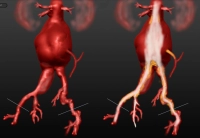

Exemplo de vídeo:

- AAA infrarrenal, diâmetro 54,2 mm

- aneurisma da artéria ilíaca comum direita, diâmetro 41,1 mm